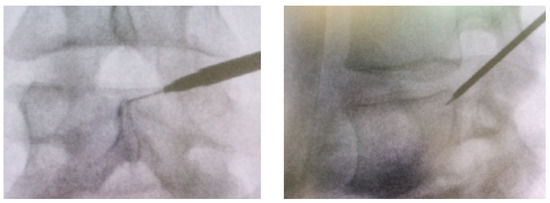

Endoscopic Foraminotomy for the Treatment of Lumbar Neuro-Foramen Stenosis: Role of CT in Treatment Planning and Post-Operative Assessment

Purpose: to outline the role of CT in pre- and post-treatment evaluation in the case of lumbar endoscopic foraminotomy. Methods: This prospective study, conducted between September 2020 and January 2024, included consecutive patients with clinical symptoms of lumbar sciatica/lumbalgia/lombo-cruralgia/lower limb peripheral neuropathy. Pre-

Purpose: to outline the role of CT in pre- and post-treatment evaluation in the case of lumbar endoscopic foraminotomy. Methods: This prospective study, conducted between September 2020 and January 2024, included consecutive patients with clinical symptoms of lumbar sciatica/lumbalgia/lombo-cruralgia/lower limb peripheral neuropathy. Pre- and post-foraminotomy CT imaging was used to assess the foraminal diameters (cranio-caudal, transverse and free hand ROI area) before and after the treatment. Two independent blinded readers assessed the CT randomly. VAS pain scale and the measurements of each foramen were compared before and after treatment. Interobserver agreement was assessed using the Intraclass Correlation Coefficient (ICC). Results: A total of 47 participants were enrolled, with 53 intervertebral levels analyzed. The mean VAS value decreased from 9.17 in the preoperative period to 0.66 at the one-month postoperative follow-up. The clinical response was associated with statistically significant changes in the cranio-caudal and transverse diameters, as well as the area of the treated neuroforamina (p-values < 0.05). Inter-rater reliability between the two operators ranged from 0.75 to 0.90. Conclusions: CT can demonstrate a significant enlargement of the neuroforaminal diameters after the endoscopic foraminotomy, with good correlation with clinical improvement.

Figure 1